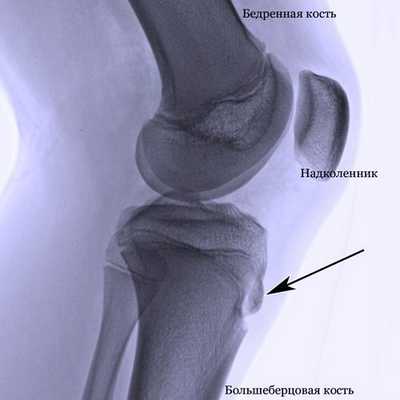

Как известно в формировании коленного сустава человека участвуют две крупные кости - бедренная (выше колена) и большеберцовая (ниже колена). В верхней части последней из них имеется особый участок (бугристость), к которому посредством сухожилия крепится четырехглавая бедренная мышца. Именно эта часть кости в детском и юношеском возрасте отвечает за ее рост и потому особо подвержена различным травмам и повреждениям. Во время активных физических нагрузок на коленный сустав в некоторых случаях приходится большая нагрузка и происходит перенапряжение четырехглавой мышцы, что приводит к растяжению или надрыву сухожилия и возникновению дефицита кровоснабжения в этой области. Вследствие такого травматического влияния и снижения питания района бугристости большеберцовой кости в ней развиваются постепенные некротические изменения, вплоть до отмирания отдельных частей ее ядра.

Рентгенография коленного сустава при болезни Осгуда-Шлаттера